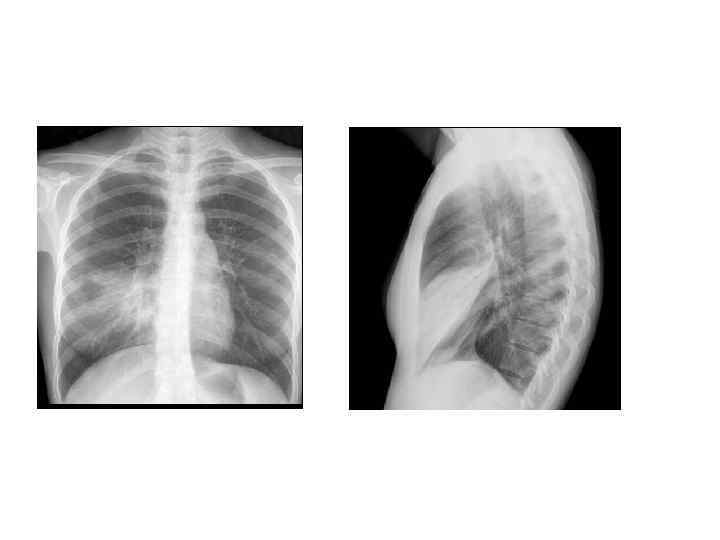

Рентгенологическая диагностика ВП • Рентген ОКГ является обязательным методом подтверждения диагноза пневмонии • Рентген ОКГ в двух проекциях должен быть проведен быстро при клиническом подозрении на пневмонию • Рентгенологический признак пневмонии – появление очаговой инфильтрации в легких

Показания к компьютерной томографии • При очевидной клинике ВП отсутствуют изменения в легких на рентгенограмме • Сложные диагностические ситуации • Затяжная пневмония (нет разрешения инфильтрата более 4 недель) • Рецидив пневмонии в той же доле